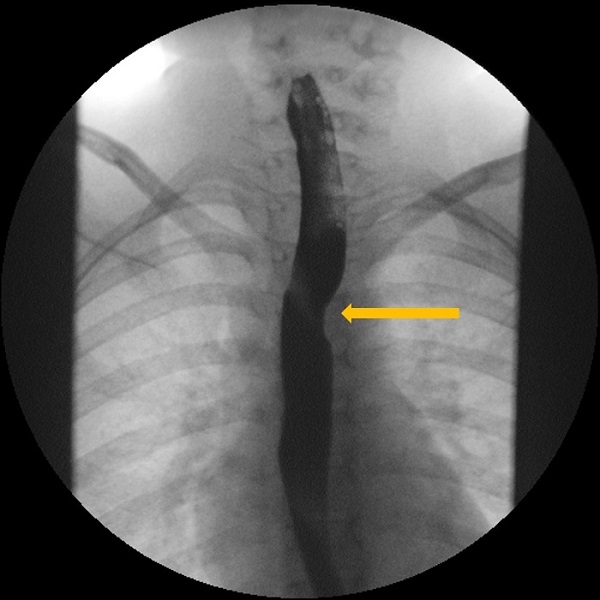

La exploración física es normal, con adecuado desarrollo ponderoestatural. Se realiza un estudio esófago-gastroduodenal con contraste baritado, en el que se pone de manifiesto una impronta sobre la pared posterior de la porción torácica del esófago, en relación con diagnóstico ya conocido de arteria subclavia derecha aberrante (Figs. 1, 2 y 3).

| Figura 3. Estudio esófago-gastroduodenal con contraste baritado. Proyección lateral. Se identifica la indentación en la pared posterior del tercio medio del esófago |

|---|

![]() |